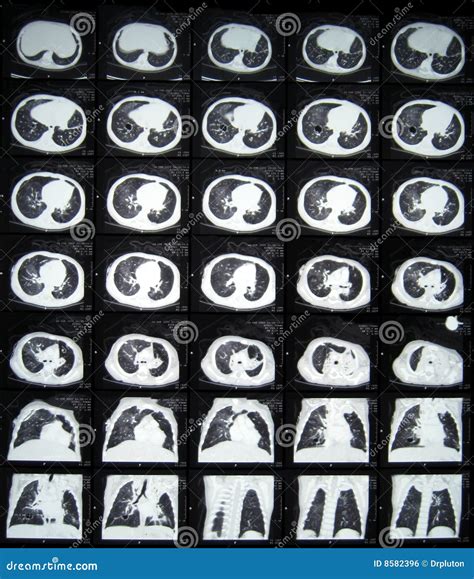

A CT of thorax, or computed tomography scan of the chest, uses X-rays and computer technology to create cross-sectional images of the thoracic cavity. These images provide a detailed view of the lungs, heart, blood vessels, and other structures within the chest. The procedure is particularly useful for diagnosing conditions such as lung cancer, pneumonia, and heart disease.

• Detailed Imaging: Provides high-resolution images of the thoracic structures.

• High-Resolution CT (HRCT): Provides detailed images of the lung parenchyma, useful for diagnosing interstitial lung diseases.